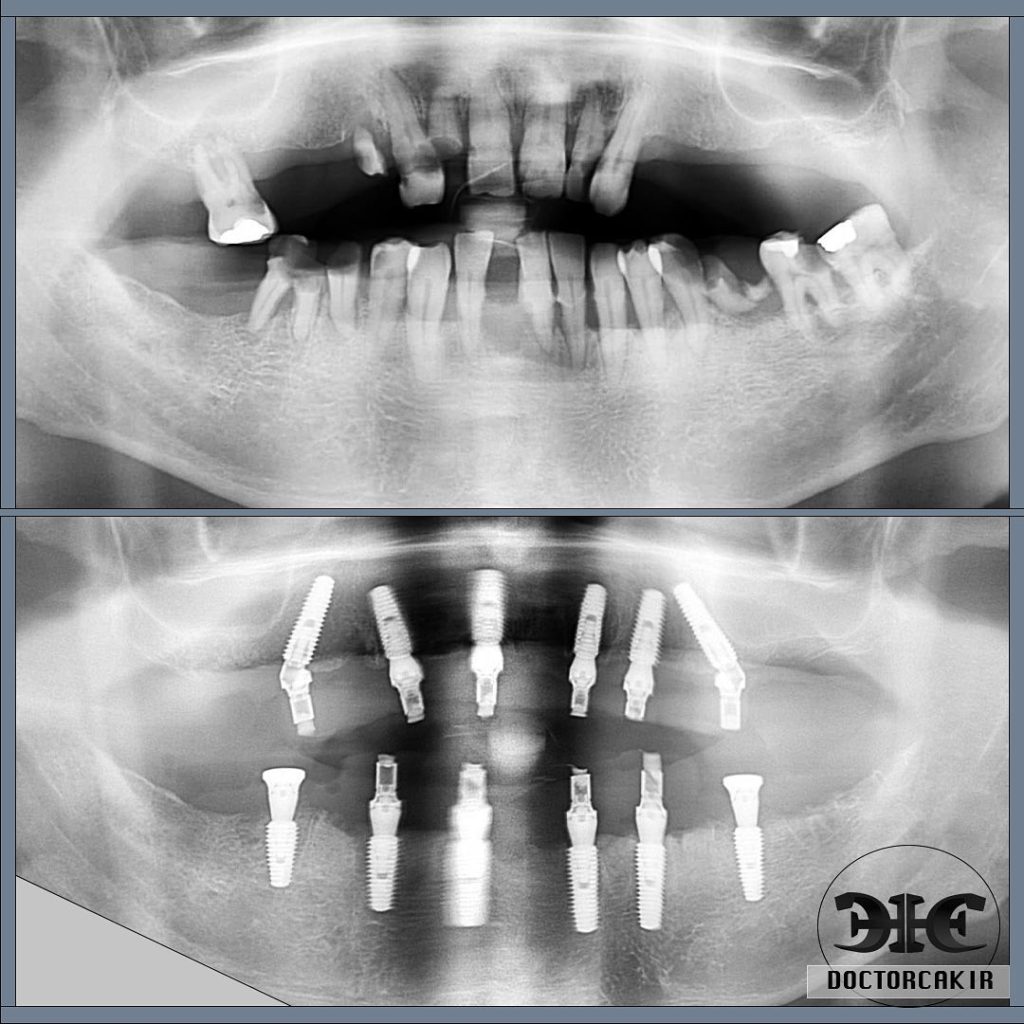

Birçok etken nedeniyle diş dokusundaki sinirler canlılığını kaybedebilir ve enfeksiyon oluşumuna açık hale gelir. Bu durumda; çevre dokuların sağlığının korunması ve enfekte dokuların meydana getirdiği ağrıların dindirilmesi için canlılığını kaybetmiş sinirlerin temizlenmesi, diş kanallarının dezenfekte edilmesi ve özel dolgu materyali ile doldurulması işlemine kanal tedavisi denir.

Kanal tedavisi gerekli olan dişlerde hastalık belirti vermeden ilerleyebilir. Bu durumda hasar radyografik muayenelerde tespit edilebilir.